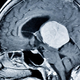

Britanec je leta spregledoval simptome, ki so kazali na tumor na možganih, dokler ga ni napad prisilil v nujno zdravljenje. Kot poroča index.hr , je 35-letni Craig Alexander več let … · Vizita.si · 2t

motnje vida vrtoglavica simptomi tumorja glavobol tumor na možganih objavi tvitaj